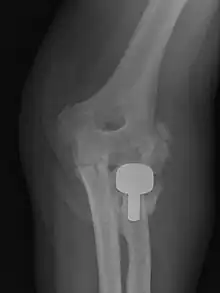

Heterotopic ossification of the elbow, after comminuted fracture and arthroplasty.

Heteropic ossification of the elbow, after comminuted fracture and arthroplasty.